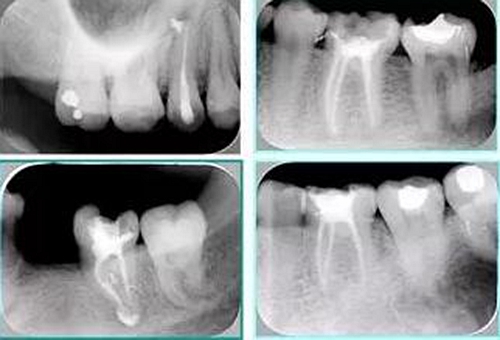

2. X 線片

共有 4 張 X 線片,分別是術(shù)前、診斷絲 、主牙膠尖確認(rèn)、術(shù)后。

( 1 )術(shù)前:術(shù)前 X 線片用來了解牙齒的大概情況。術(shù)前預(yù)期為多根牙時(shí) X 線片應(yīng)偏頭拍攝。

( 2 )診斷絲:根據(jù)術(shù)前 X 線片進(jìn)行開髓、根管的初步預(yù)備后,需要插入診斷絲,用來指示工作器械位置。常用 10 號(hào)或 15 號(hào)擴(kuò)大器作為診斷絲插入牙髓腔。

( 3 )主牙膠尖確認(rèn):通過術(shù)前預(yù)期和診斷絲診斷,明確工作長(zhǎng)度、牙根走向,進(jìn)行根管預(yù)備。之后應(yīng)進(jìn)行主牙膠尖(中銼)確認(rèn),已明確根管是否適合充填。

( 4 )術(shù)后:觀察治療效果。